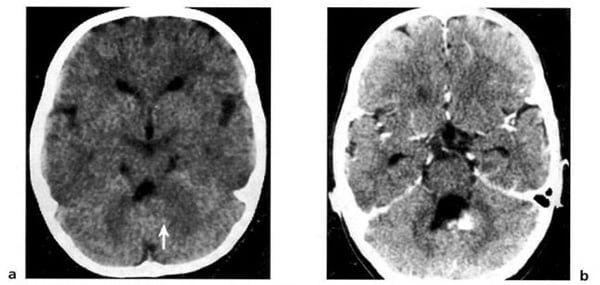

Hình 1.54. U tế bào hình sao (độ 1) ở tiểu não của một trẻ 5 tuổi. Trước tiêm (a), u có mật độ thấp và hiện lên như dạng nang hoàn toàn. Sau tiêm (b), phần đặc bắt chất cản quang.

Hình 1.55. U tế bào hình sao (độ 2) ở một trẻ 2 tuổi. Trước tiêm (a), u có mật độ thấp đặc trưng (mũi tên). Thành phần đặc bắt rõ chất cản quang (b). Não úng thủy do tắc nghẽn.